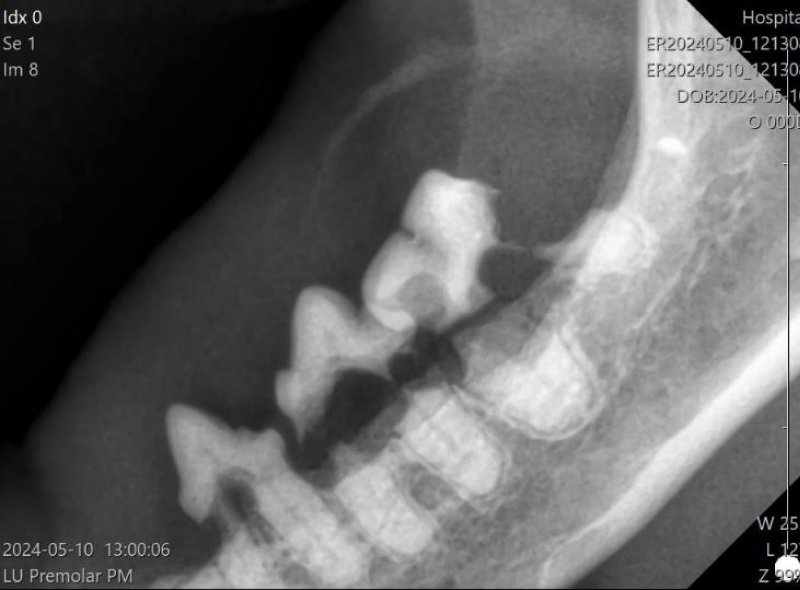

顎骨折(歯周病による下顎骨折)

歯周病や交通事故、衝突などにより、顎の骨を骨折してしまうことがあります。

特に、小型犬種では、顎と歯の大きさが相対的に近くなるため、歯周病が進行した時、下顎骨が吸収(溶けて)骨折することがあります。

治療は、歯周病の治療を行い、病因となっている歯は抜歯し、固定に使えそうな歯または支持組織が残っている場合にはそれを利用して固定を行います。

骨折は、骨折端を合わせて固定することで、約1ヶ月で癒合してきます。

ただし、口は常に動かして使う組織ですので、“固定”が難しく、その治癒が難しいことがあります。